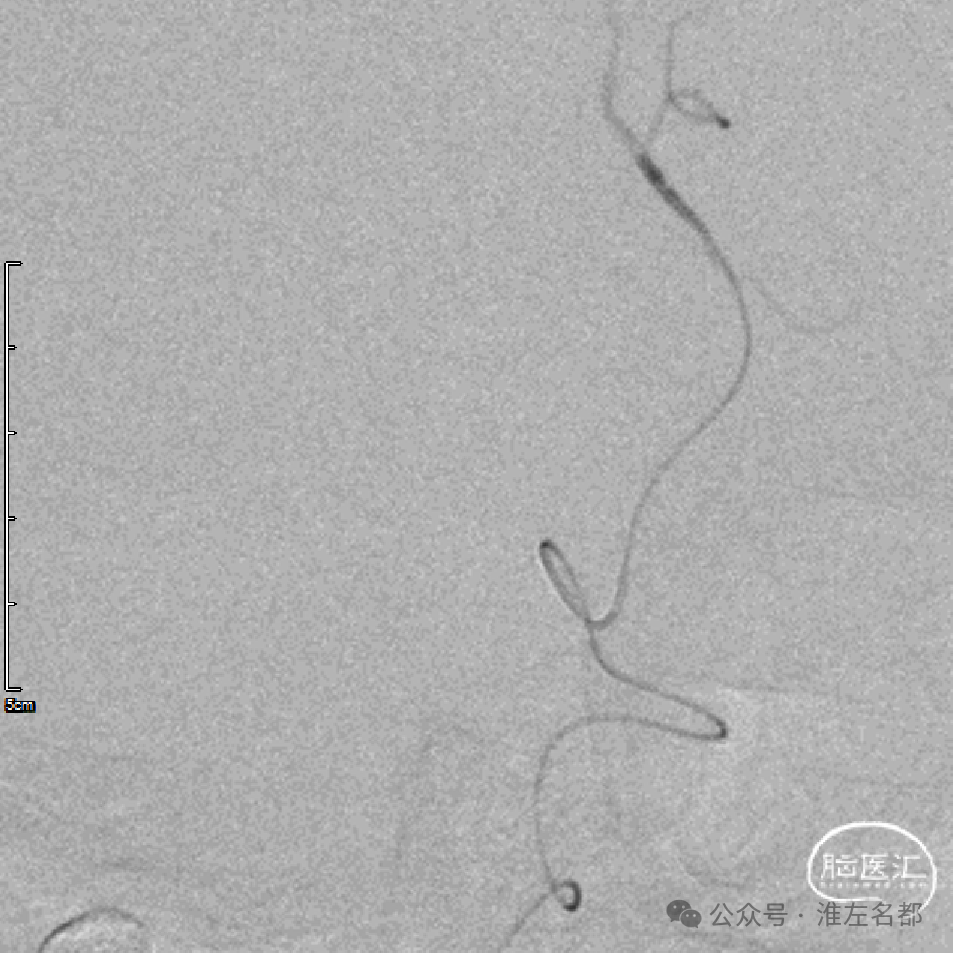

急诊血管内介入治疗

微导管通过闭塞位置,造影证实位于真腔。

取出少量血栓